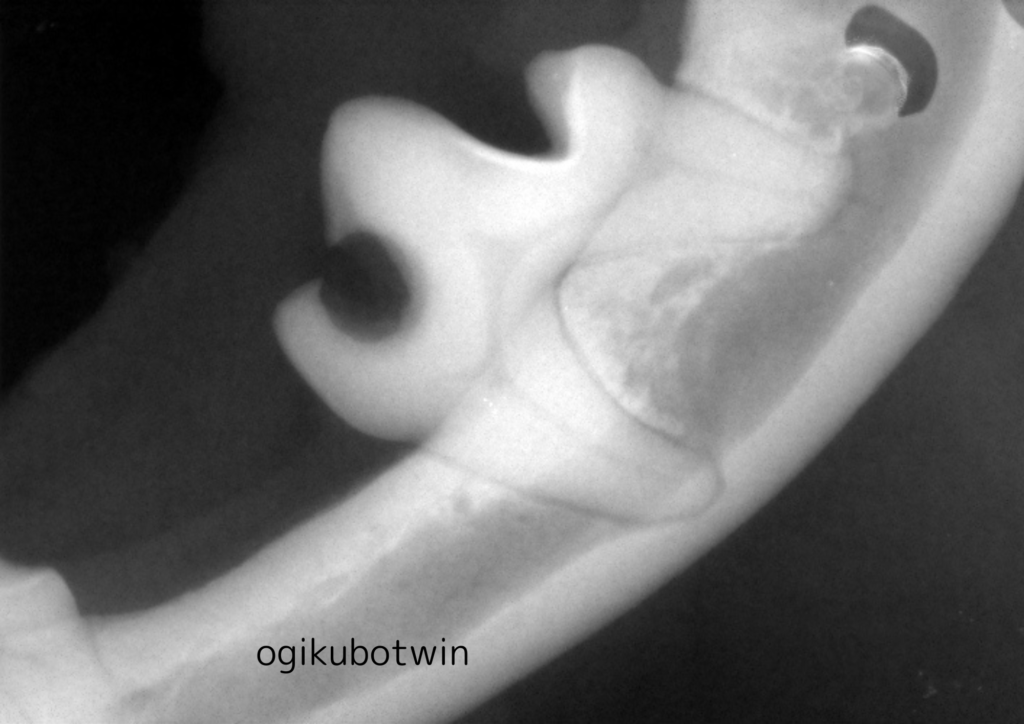

全身麻酔下にて歯科レントゲンを撮影し虫歯になっている歯を抜歯しました。

レントゲンでも歯に大きく穴が開いていることがわかります。

歯周病になっていて残せないと判断した歯も同時に抜歯しています。